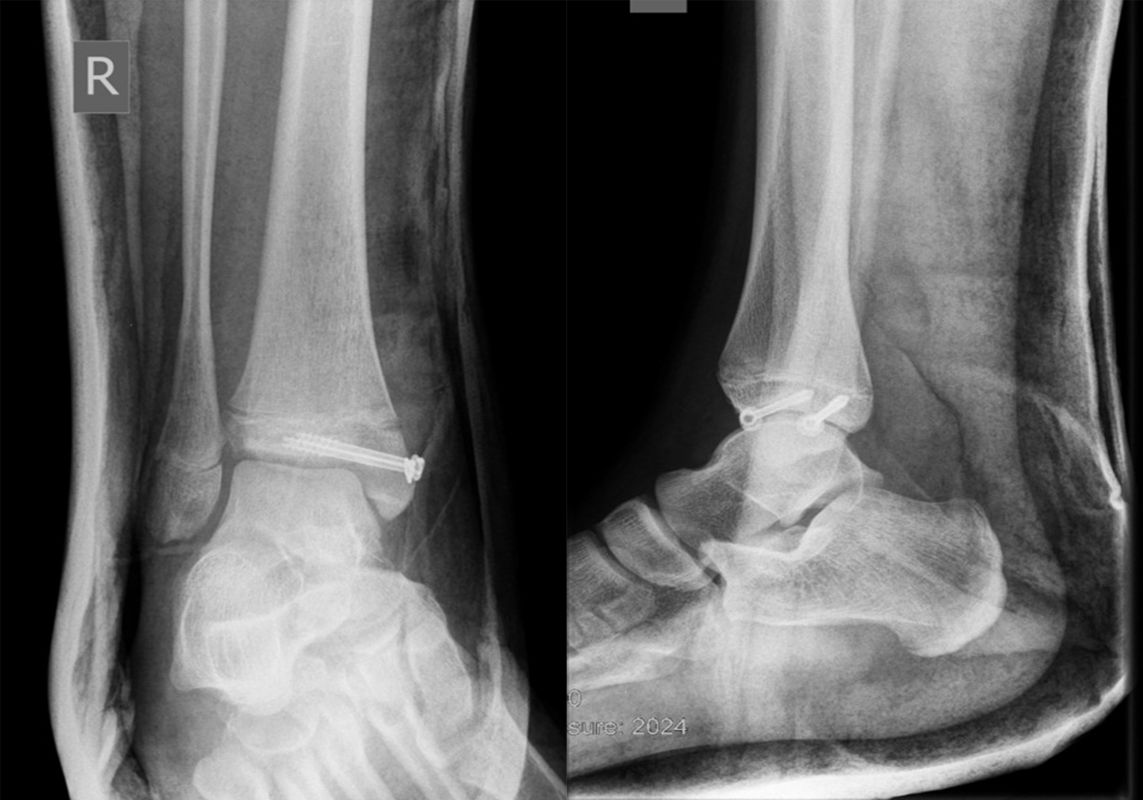

Behandlungsziel ist die exakte Rekonstruktion der Gelenkfläche sowie die Minimierung des Risikos einer späteren Wachstumsstörung. Dislozierte Frakturen werden offen reponiert, die Osteosynthese erfolgt mit einer Kleinfragmentschraube. Finden sich viele kleine Fragmente kann eine K-Draht Osteosynthese durchgeführt werden. Wird der Innenknöchel operiert, kann bei gleichzeitiger hochgradiger lateraler Instabilität eine Rekonstruktion des lateralen Bandapparats durchgeführt werden. Fibula Frakturen stellen sich meist spontan ein, sodass hier keine zusätzliche Osteosynthese notwendig ist.

Nach der Osteosynthese wird die Fraktur für ca. vier Wochen in einem Unterschenkelgips ruhiggestellt. Bei Schmerzfreiheit der Frakturzone erfolgt anschließend eine schmerzadaptierte Belastungssteigerung über weitere zwei Wochen. Sobald unter Alltagsbedingungen Beschwerdefreiheit besteht kann die sportliche Belastung langsam gesteigert werden. Kirschnerdrähte werden 6-8 Wochen postoperativ, Schrauben nach zwölf Wochen entfernt. Es empfiehlt sich klinische und radiologische Kontrollen im Abstand von 6 Monaten bis zum Wachstumsabschluss durchzuführen, um ein mögliches Fehlwachstum frühzeitig zu erkennen.

Dislozierte Frakturen (Frakturspalt > 2 mm) werden grundsätzlich operativ behandelt. Die Reposition kann arthroskopisch unterstützt erfolgen. Die Schraubenosteosynthese erfolgt entsprechend dem Frakturverlauf. Bei Twoplain Frakturen ist meist eine epiphysäre Schraube ausreichend die von lateral kommend das Fragment nach medial-proximal fixiert. Der Schraubenverlauf ist üblicherweise von lateral ventral nach proximal dorsal medial (Abb. 24). Nach Reposition darf in der seitlichen Aufnahme des Sprunggelenks, als auch in der 45° Außenrotationsaufnahme keine Stufe in Höhe der Wachstumsfuge erkennbar sein. Eine sichtbare Stufe ist Indikator für eine unzureichende Reposition.